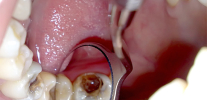

Foto de um dente com uma cárie profunda que atinge a câmara pulpar:

Geralmente, no dente, há uma cavidade profunda e cárie com dentina infectada amolecida, que freqüentemente se comunica com a câmara pulpar.Para esclarecer a presença dessa mensagem, o dentista usa uma sonda - um instrumento de metal curvo e afiado no final da sondagem.

Durante esse procedimento, fica claro se há uma mensagem no fundo da cavidade com a polpa do dente. Se houver uma mensagem, depois de sentir a polpa, muitas vezes começa a sangrar dolorosamente.